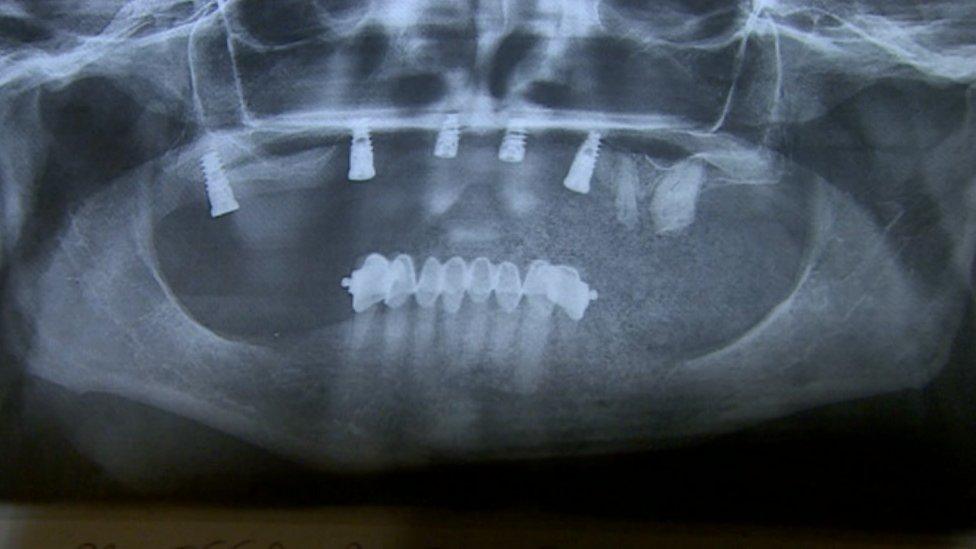

Mrs Stokes had implants in her upper jaw and crowns on eight teeth in her lower jaw, over two trips to Budapest.

On her second visit in June 2013, she said she was left with a "bulldog bite" - a gap between her gums and upper teeth through which food would seep.

The Forest and Ray Medical Care Group's London clinic said all Jackie Stokes' implants needed to be taken out in July 2014

The implants failed and were later removed. She now has to wear dentures.